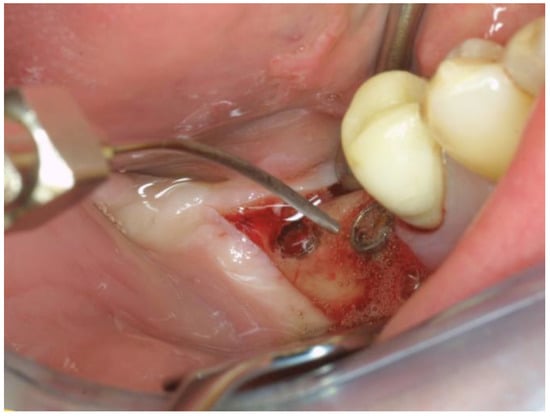

The OHLLT surgical procedure consists of (Figure 2 and Figure 3): local anesthesia; intrasulcular incision for a full thickness periodontal flap; mechanical instrumentation and removal of necrotic tissues with Gracey curettes; ultrasonic instrumentation for supra- and subgingival scaling combined with water–Betadine irrigation (5:1 ratio); air flow device with sodium bicarbonate powder (highly abrasive powder).

Figure 2. Full Thickness Flap.